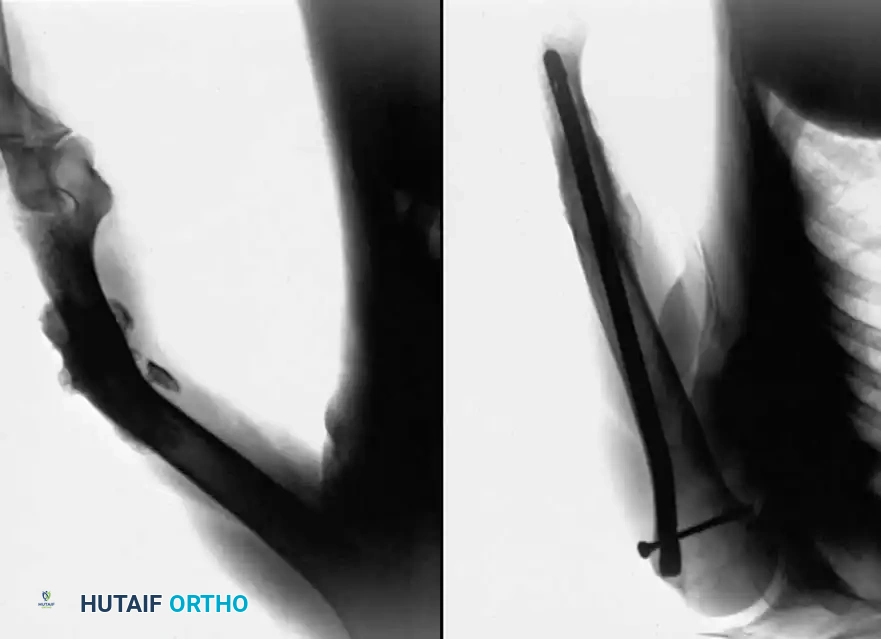

Fig. 56-19 Technique for grafting nonunion of medial malleolus (Banks).

Postoperative Protocol: The aftertreatment is identical to that of the sliding graft technique.